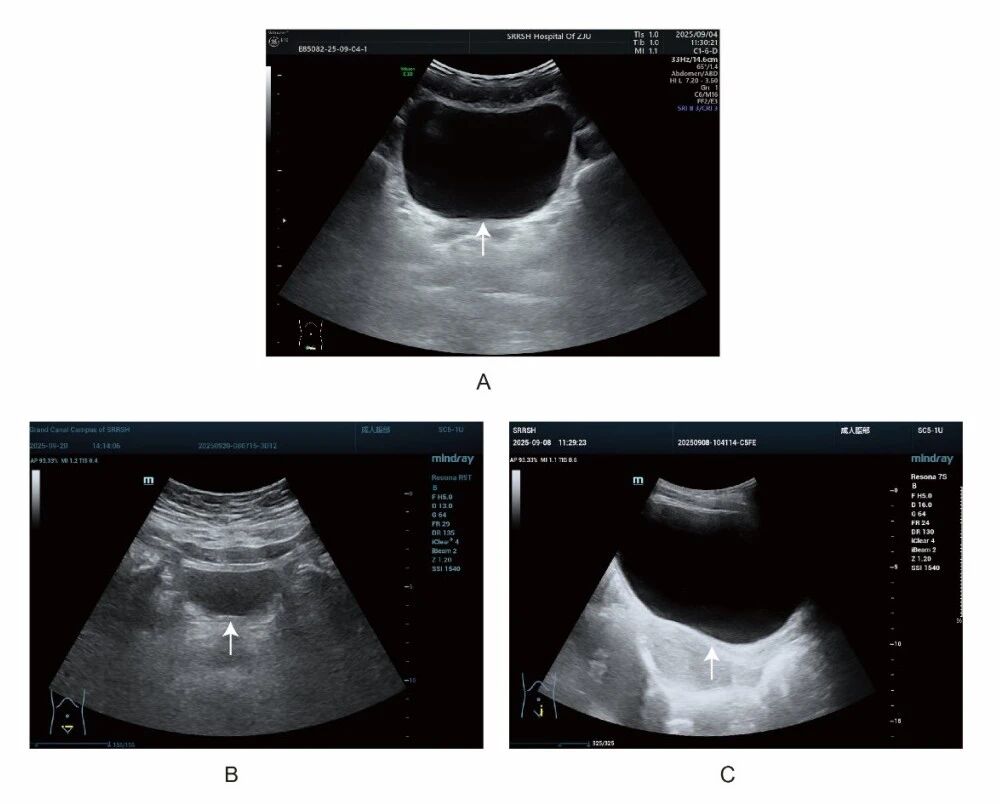

(白色箭头所指为“膀胱”,A:充盈适宜的膀胱,B:充盈欠佳的膀胱,C:充盈过度的膀胱)